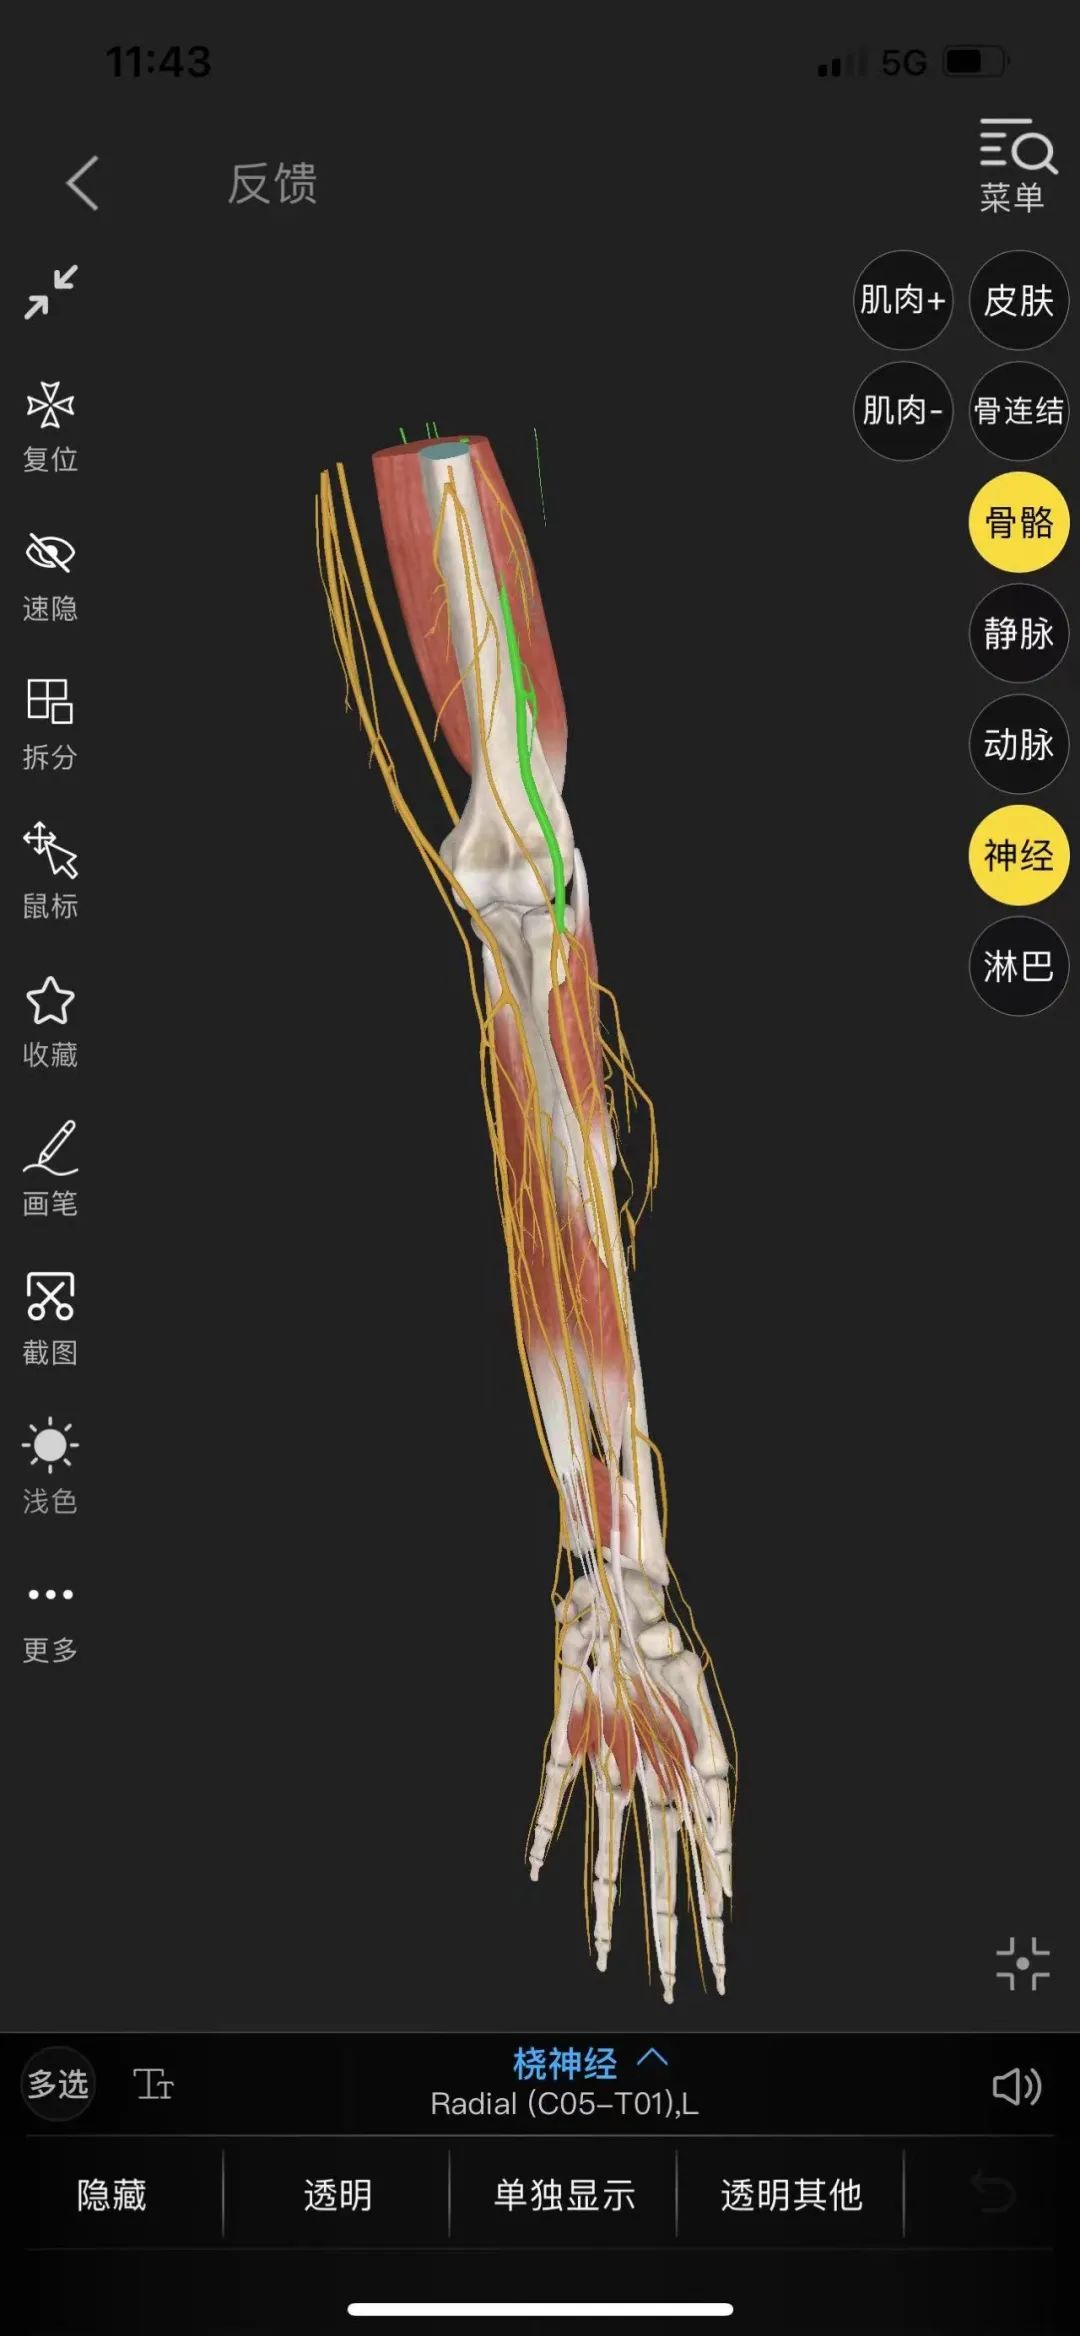

近日,我院西区手麻科就接诊一位仅有六月龄大的先天性右手六指畸形患儿。当下确保患儿术中安全及术后镇痛的问题便成了医生首要考虑的因素。面对如此超低龄患儿,麻醉医生王晓天主任医师及主诊医生邱坤副主任医师经术前慎重评估及家属同意后,决定一改往日常规气管插管全身麻醉或静脉复合全身麻醉这两种麻醉方式,而采取超声引导下肘上桡神经阻滞技术。26日上午10:35分患儿被推入手术室,得到充分镇静后,为其进行超声引导下肘上桡神经阻滞,阻滞顺利11:10手术开始,历时40分钟手术顺利结束,患儿安返病房。后经访视,患儿情况稳定。

神经阻滞技术也是临床麻醉中常用的镇痛方式,它不但能降低并发症引发的风险,而且能增加患者的满意度和舒适度,促进患者的快速康复。